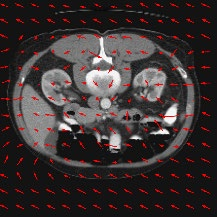

Transformers have made remarkable progress towards modeling long-range dependencies within the medical image analysis domain. However, current transformer-based models suffer from several disadvantages: (1) existing methods fail to capture the important features of the images due to the naive tokenization scheme; (2) the models suffer from information loss because they only consider single-scale feature representations; and (3) the segmentation label maps generated by the models are not accurate enough without considering rich semantic contexts and anatomical textures. In this work, we present CASTformer, a novel type of generative adversarial transformers, for 2D medical image segmentation. First, we take advantage of the pyramid structure to construct multi-scale representations and handle multi-scale variations. We then design a novel class-aware transformer module to better learn the discriminative regions of objects with semantic structures. Lastly, we utilize an adversarial training strategy that boosts segmentation accuracy and correspondingly allows a transformer-based discriminator to capture high-level semantically correlated contents and low-level anatomical features. Our experiments demonstrate that CASTformer dramatically outperforms previous state-of-the-art transformer-based approaches on three benchmarks, obtaining 2.54%-5.88% absolute improvements in Dice over previous models. Further qualitative experiments provide a more detailed picture of the model's inner workings, shed light on the challenges in improved transparency, and demonstrate that transfer learning can greatly improve performance and reduce the size of medical image datasets in training, making CASTformer a strong starting point for downstream medical image analysis tasks.